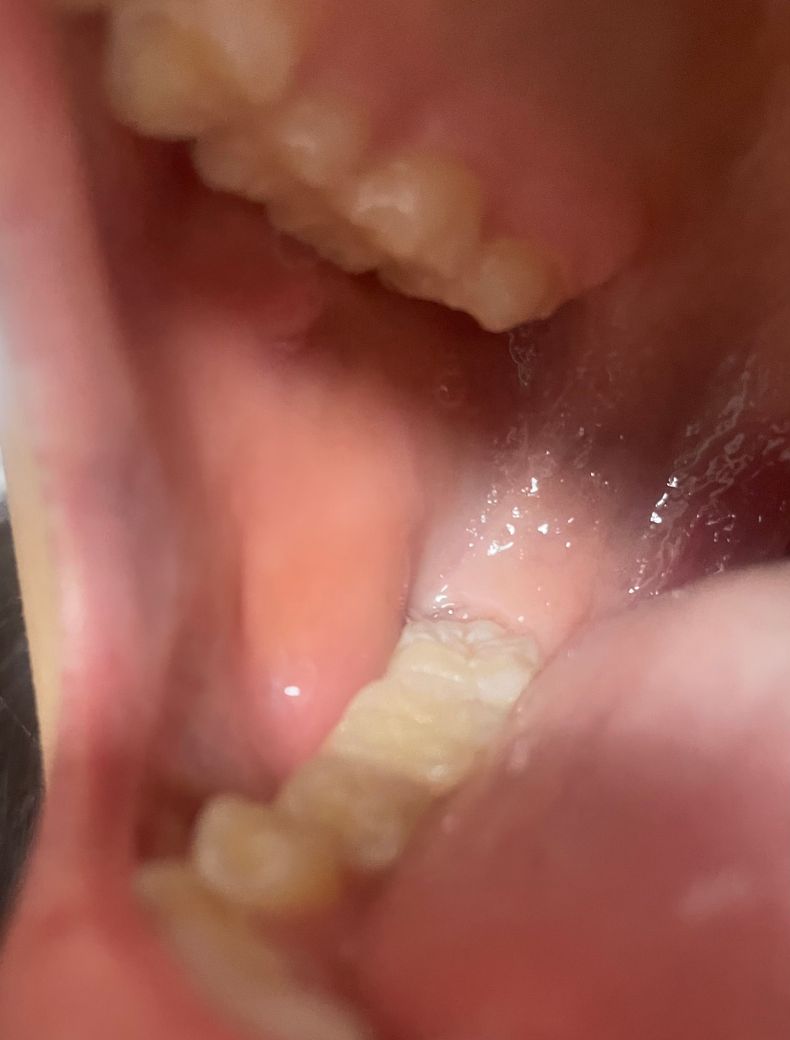

• 2번 째 사진

우리 몸에 존재하는 정상적인 타액선으로 보여집니다. 다만 사진만으로는 정확한 판단이 어려우며 너무 불안하시다면 가까운 치과 방문 후 검사를 한 번 해보시길 바랍니다. 사진으로는 parotid gland일 가능성이 있어 보입니다.

대단한건 아닌거 같습니다. 볼살이 씹혀서 과증식 된거 같습니다. 걱정하지 않으셔도 될것같습니다.